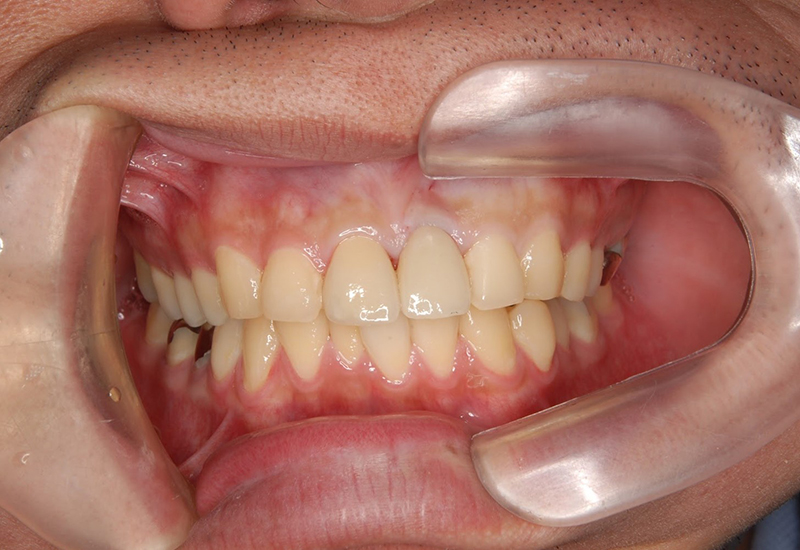

治療前後の写真

治療後 |

治療後